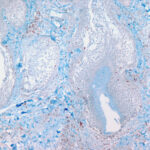

The mucin found in these six diseases represents an increase in the mucin that is normally present in the ground substance of the dermis. It consists of proteins bound to hyaluronic acid (hyaluronan), which is an acid mucopolysaccharide or glycosaminoglycan. As a result of the great water-binding capacity of hyaluronic acid, dermal mucin contains a considerable amount of water. This water is largely removed during the process of dehydration of the specimen; consequently, in routine sections, the mucin, because of its marked shrinkage, appears largely as threads and granules. |

The mucin present in the six types of mucinosis stains a light blue in sections stained with H&E. It also stains with colloidal iron. It is Alcian blue-positive at pH 2.5 but negative at pH 0.5 and shows metachromasia with toluidine blue at pH 7.0 and 4.0 but no metachromasia below pH 2.0 . It is PAS negative (indicating the absence of neutral mucopolysaccharides) and aldehyde fuchsin negative (indicating the absence of sulfated acid mucopolysaccharides). The mucin is completely removed on incubation of histologic sections with testicular hyaluronidase for 1 hour at 37″C . |